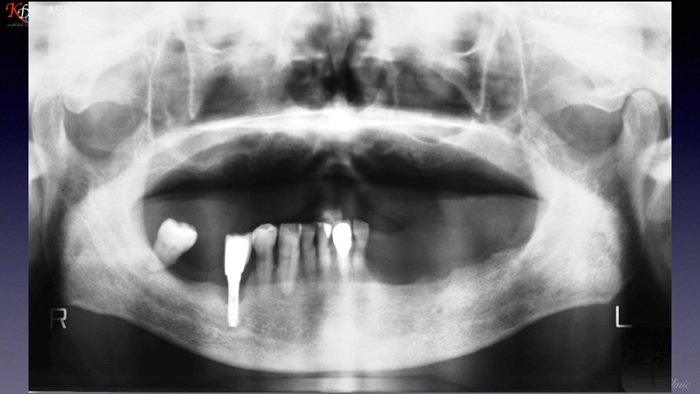

咬合再建・咬合回復shapeimage_22_link_0

症例に応じた治療手法の選択と咀嚼機能再現の効果http://www.kura-dent.com/Treatment%20and%20effects.pdfshapeimage_23_link_0